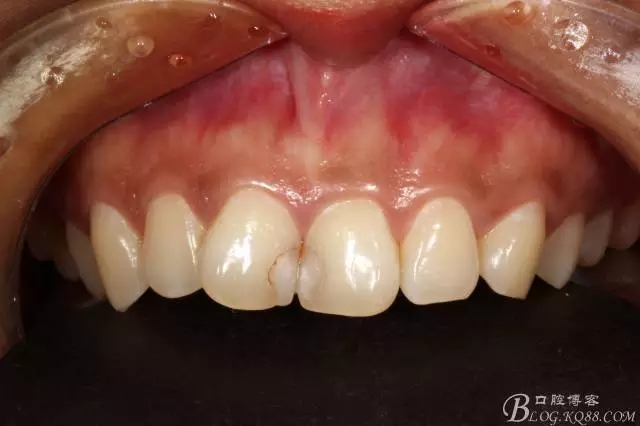

2012年2月接診是的情況